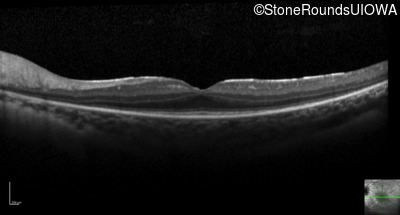

Optical Coherence Tomography - Left - 20/63 +1

Exemplar / OCT Stack